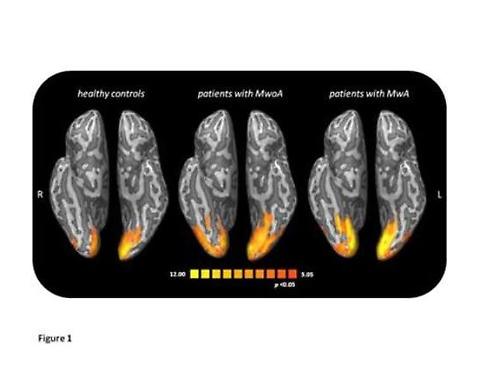

L’emicrania si caratterizza per un dolore e moderato-severo pulsante che spesso si localizza nella metà della testa e del volto. Il paziente non riesce a svolgere nessuna delle attività quotidiane perché ogni azione aggrava il dolore e, a volte (emicrania con aura), gli attacchi vengono preceduti da disturbi neurologici come ad esempio sintomi visivi. La crisi si manifesta solitamente insieme ad altri disturbi come vomito e intolleranza alla luce e ai rumori e può durare da alcune ore a 2-3 giorni.